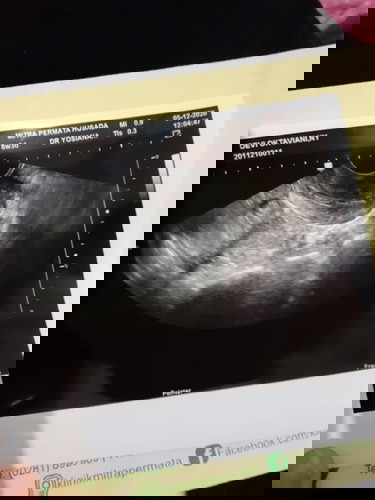

Alhamdulillah saya sdg hamil anak pertama UK 7w, cuma seminggu kemarin sempet keluar flek dan darah seperti haid. Takut banget kata dokter bisa ikut luruh kantung janinnya, diminta buat balik 2 mggu lagi. Saya jadi kepikiran terus sampe berkali kali tespek karena takut kenapa kenapa janinnya. Kadang jd mikir yg aneh aneh. Bunda semua apakah punya tips supaya tetap tenang dan mengurangi rasa cemas? Mohon doanya jg semoga janin dan ibunya sehat aamiin #pregnancy

Mohon doanya ya bunda semua... saya hamil 6 weeks tapi keluar flek. Saat periksa, alhamdulillah masih ada kantung janin kata dokter tapi ada perdarahan dan terancam keguguran sehingga harus bedrest total.. Awalnya sedikit dan berwarna coklat, tapi lama lama netes seperti darah haid dan ada darah beku sedikit yg keluar. Saya takut banget sampai berpikir yang aneh aneh, sempet pinsan juga kemarin. Tp pagi tadi saya tespek alhamdulillah masih 2 garis. Mohon doanya ya bun semoga janin saya sehat, kuat dan bisa berkembang dengan baik. Semoga perdarahannya juga bisa berhenti karena sampai skrg masih keluar :") #firstbaby #pregnancy #mohondoanya